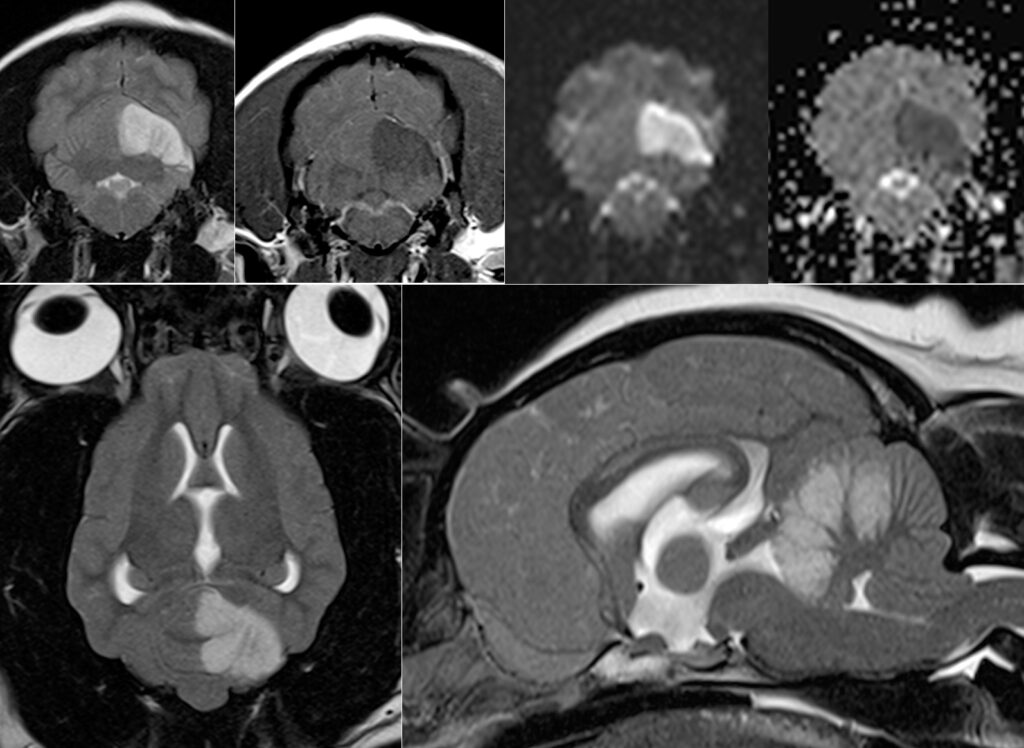

Figue 1. IRM d’un AVC ischémique cérébelleux rostral chez un cavalier King Charles spaniel.

De gauche à droite, haut : séquences transverses T2, T1, diffusion, ADC.

De gauche à droite, bas : séquences T2 dorsale et sagittale.

Noter l’aspect bien délimité sans effet de masse de la lésion sur toutes les séquences

Les AVC ischémiques sont visibles en IRM dès les premières heures après leur survenue et se caractérisent par une lésion hyperintense en séquence T2, hypointense en séquence T1, à bords nets, un effet de masse faible à modéré et une prise de contraste tardive (maximale vers 7-10 jours). Ajoutées aux séquences conventionnelles, les séquences de diffusion permettent d’augmenter la performance de l’IRM (Figure 1) et sont utiles pour distinguer les AVC ischémiques des tumeurs gliales pouvant parfois mimer un AVC.